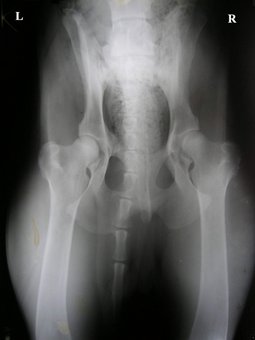

Sąnarių problemos - 2: Displazija, degeneracija

Erke, va palygink su savo. 1 sveikas, 2 sunkus laipsnis, 3 kaire...